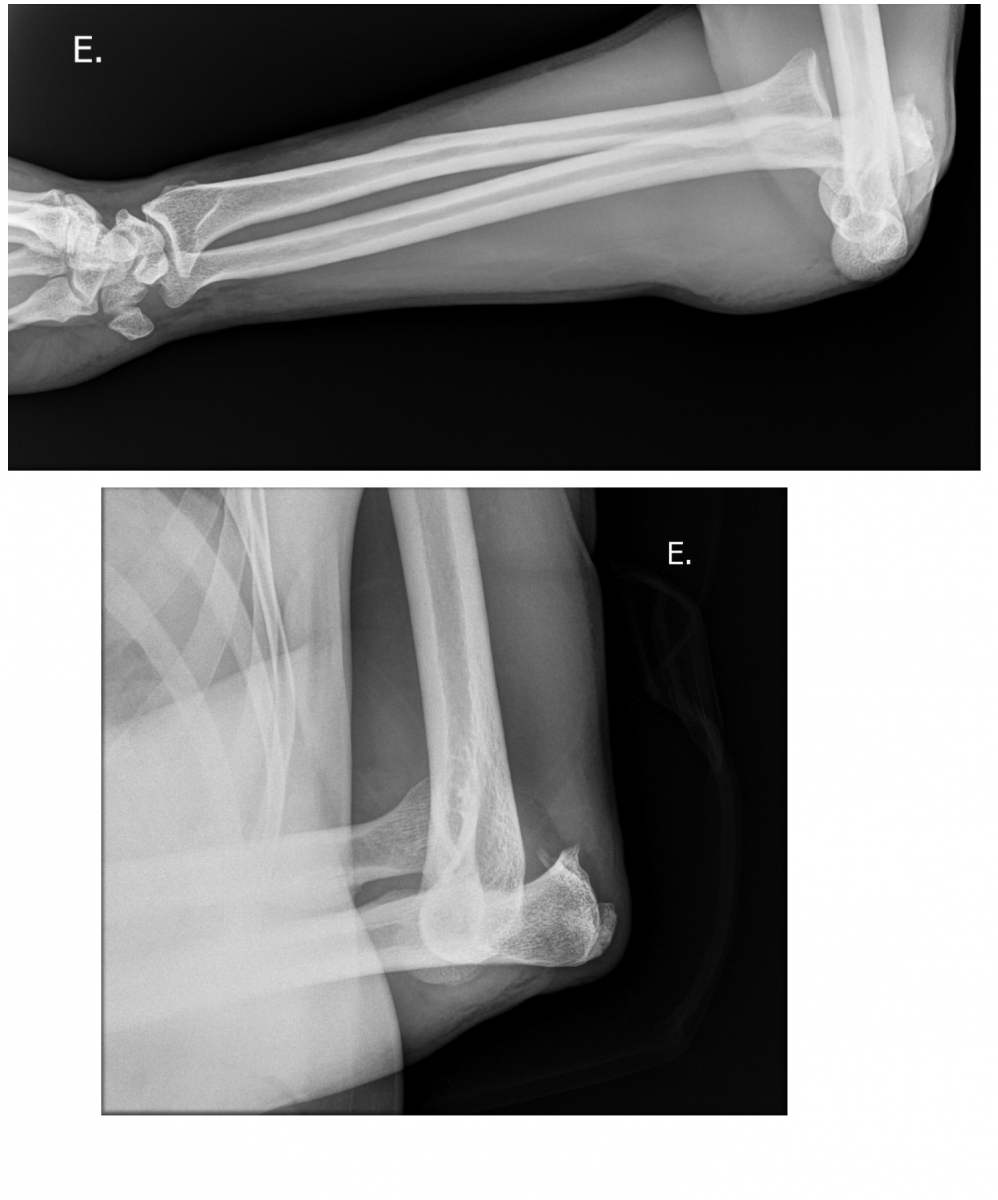

Se trata de un paciente de 61 años de edad que sufrió una luxación de codo izdo, tras caída desde una altura, en marzo del 2018. Tras la reducción de la luxación, se constató un codo inestable por arrancamiento del Lig. Colateral Medial y del tendón conjunto de la musculatura flexora-pronadora. El paciente fue intervenido a la semana del accidente, procediendo a la reinserción y reparación del complejo ligamentoso y tendinoso mediante anclajes óseos.

Debido a la lesión y a su posterior inmovilización, inevitable para la cicatrización de las partes blandas, el codo evolucionó a una rigidez articular importante.

Tras 4 meses de rehabilitación, el rango de movilidad obtenido fue pobre, por lo que ingresó de nuevo para Artrolisis artroscópica y colocación de un catéter axilar para rehabilitación en planta, consiguiendo tras el ingreso, una movilidad aceptable, que fue incrementando en los meses sucesivos hasta llegar a ser prácticamente completa.